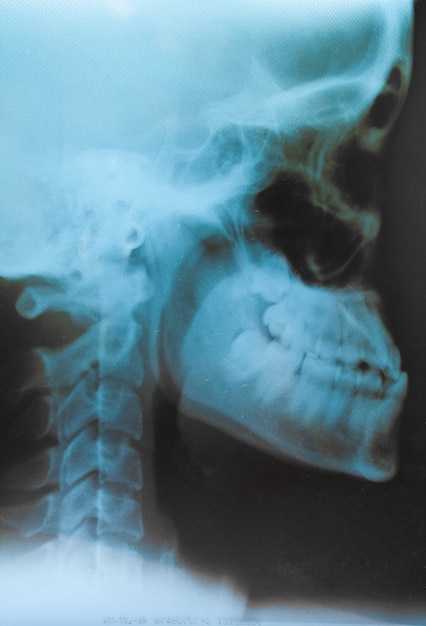

- Снимки в профиле: Позволяют увидеть обе пазухи одновременно и оценить симметричность их состояния.

Роль боковых проекций в диагностике гайморита

Боковые проекции играют значительную роль в определении наличия воспалительных процессов в верхнечелюстных пазухах. Они позволяют детально оценить состояние носовых проходов и прилегающих структур.

При выполнении боковой проекции возможно:

- Определить уровень жидкости в пазухах, что указывает на наличие воспалительного экссудата.

- Выявить затенение, характерное для воспалительных процессов, что поможет отличить острые и хронические формы патологии.

- Оценить состояние стенок пазух, что может свидетельствовать о стенозе или шунтировании.

Анализ боковых проекций позволяет установить диагноз более точно и выбрать оптимальную стратегию лечения. Учитывая каждый из этих факторов, специалист сможет эффективно идентифицировать патологические изменения и предложить целенаправленное вмешательство.